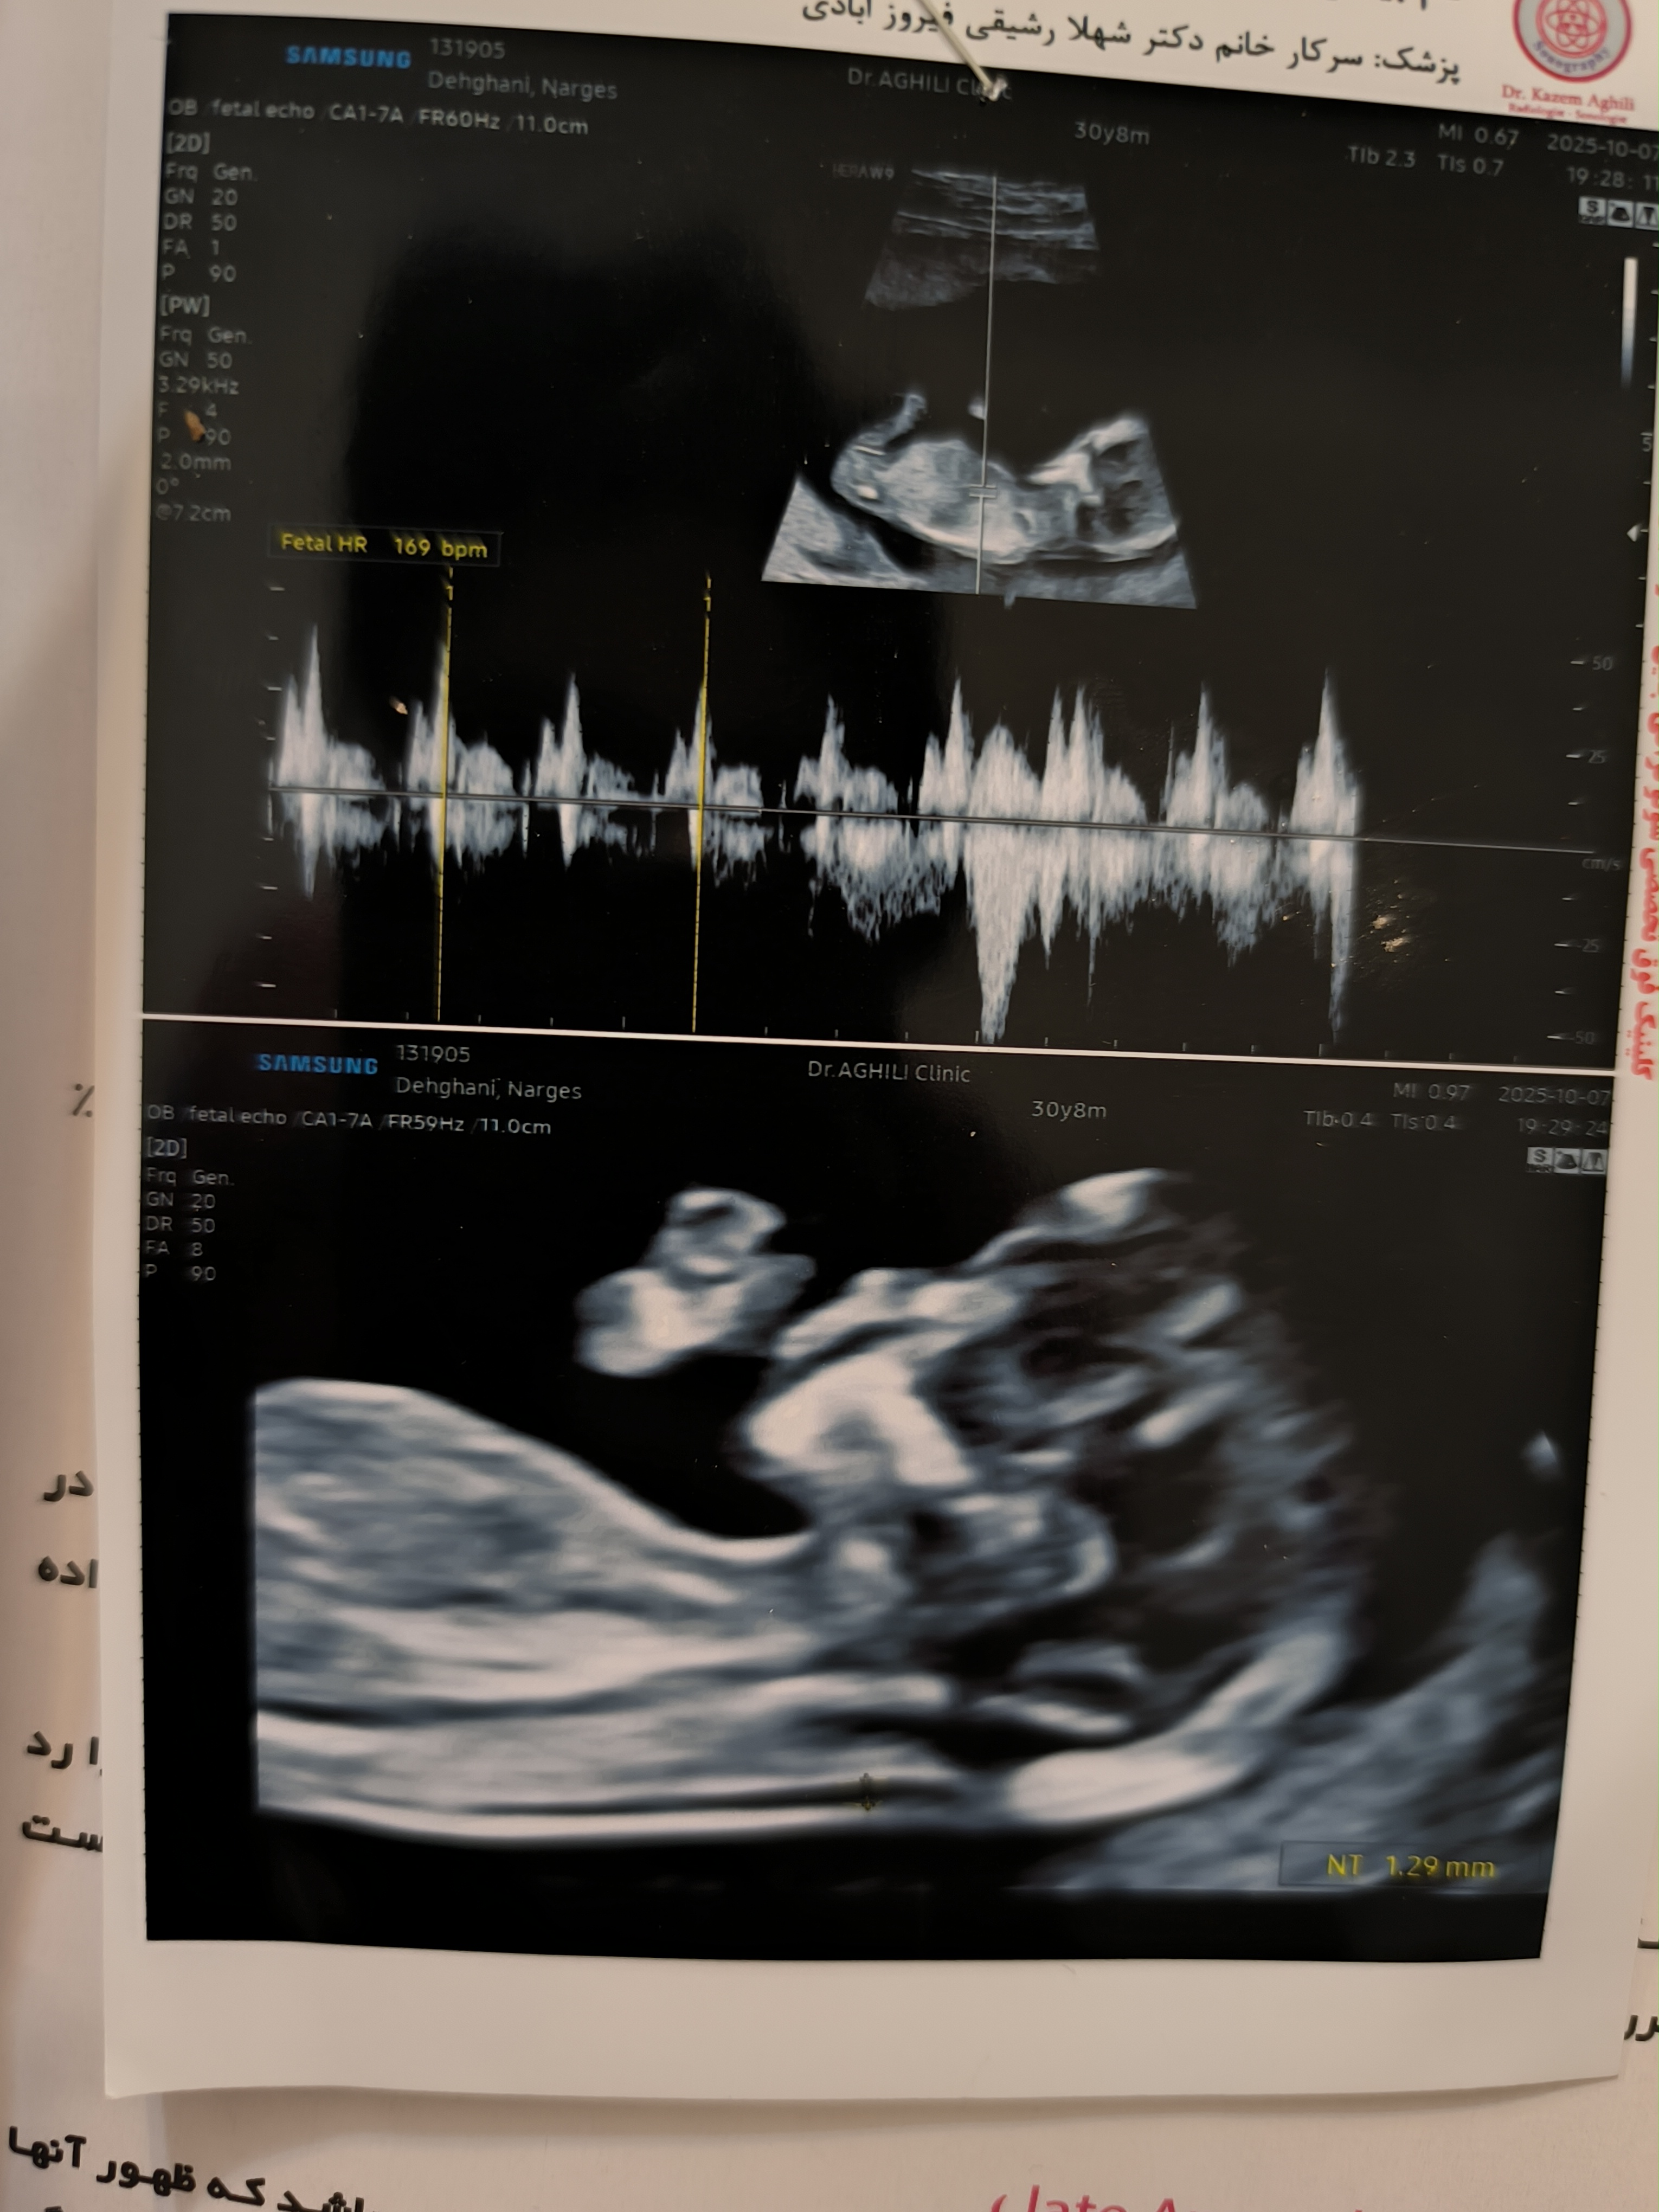

اگه ضربان قلب زیر ۱۶۵ هست پسره اگه ۱۶۵ دختره و باید منتظر سونو ان تی باشی دقیق نمیشع امیدوار کرد کسی ...

واسه نینی من ۱۷۲ بود پسر عزیزم

بنظرتون دختره؟

همینجا میگفتن اگه جلو پیشانی گرد باشه دختره اگه شیب داشته باشه پسره منم عکس سنو گذاشتم پیشانیش شیب داره و پسر شد الانم ۸ماهشه داره شیر میخوره عکسش پروفایلمه😍😁